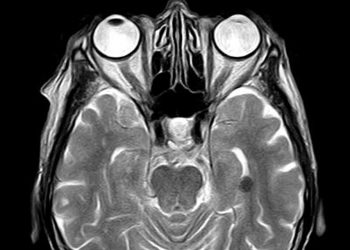

Studi: Kerusakan Otak COVID-19 Mirip Dengan yang Disebabkan oleh Stroke

ChanelMuslim.com - Menurut sebuah studi terbaru menyatakan bahwa kerusakan otak yang disebabkan oleh COVID-19 mirip dengan yang disebabkan oleh stroke. ...